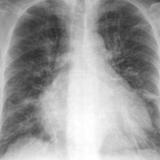

Bivent failure

Date: 11/05/2005

Views: 2532

IPE 1

Views: 2674